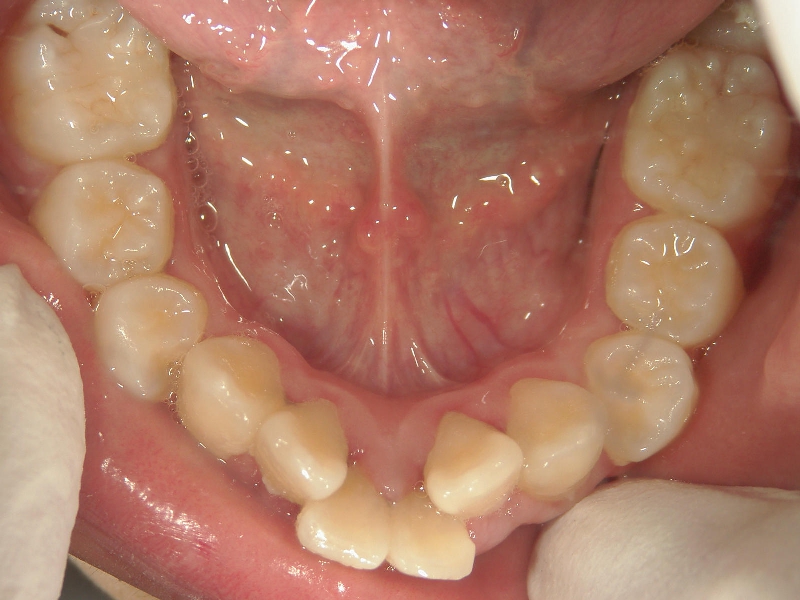

矯正_灰色.pngno.18_2196_治療前_下.jpg矯正_灰色.png

矯正_灰色.pngno.18_2196_治療後_下.jpg矯正_灰色.png